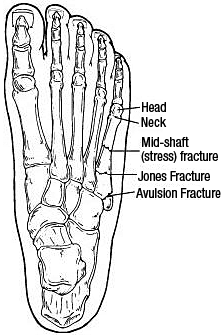

The fifth metatarsal is divided into the base, the tuberosity, the shaft (diaphysis), the neck and the head. The tuberosity, also termed the styloid process, is a bony prominence just distal to the base. Both the peroneus brevis and peroneus tertius have insertions adjacent to this prominence. The plantar fascia also has a focused insertion on the proximal tip of the fifth metatarsal. The distal metaphysis tapers to the tubular diaphysis of the fifth metatarsal. Fractures commonly occur at this metatarsal shaft, within 1.5 cm of the tuberosity.

Fig. 3: Location and orientation of fracture determines type of fracture.